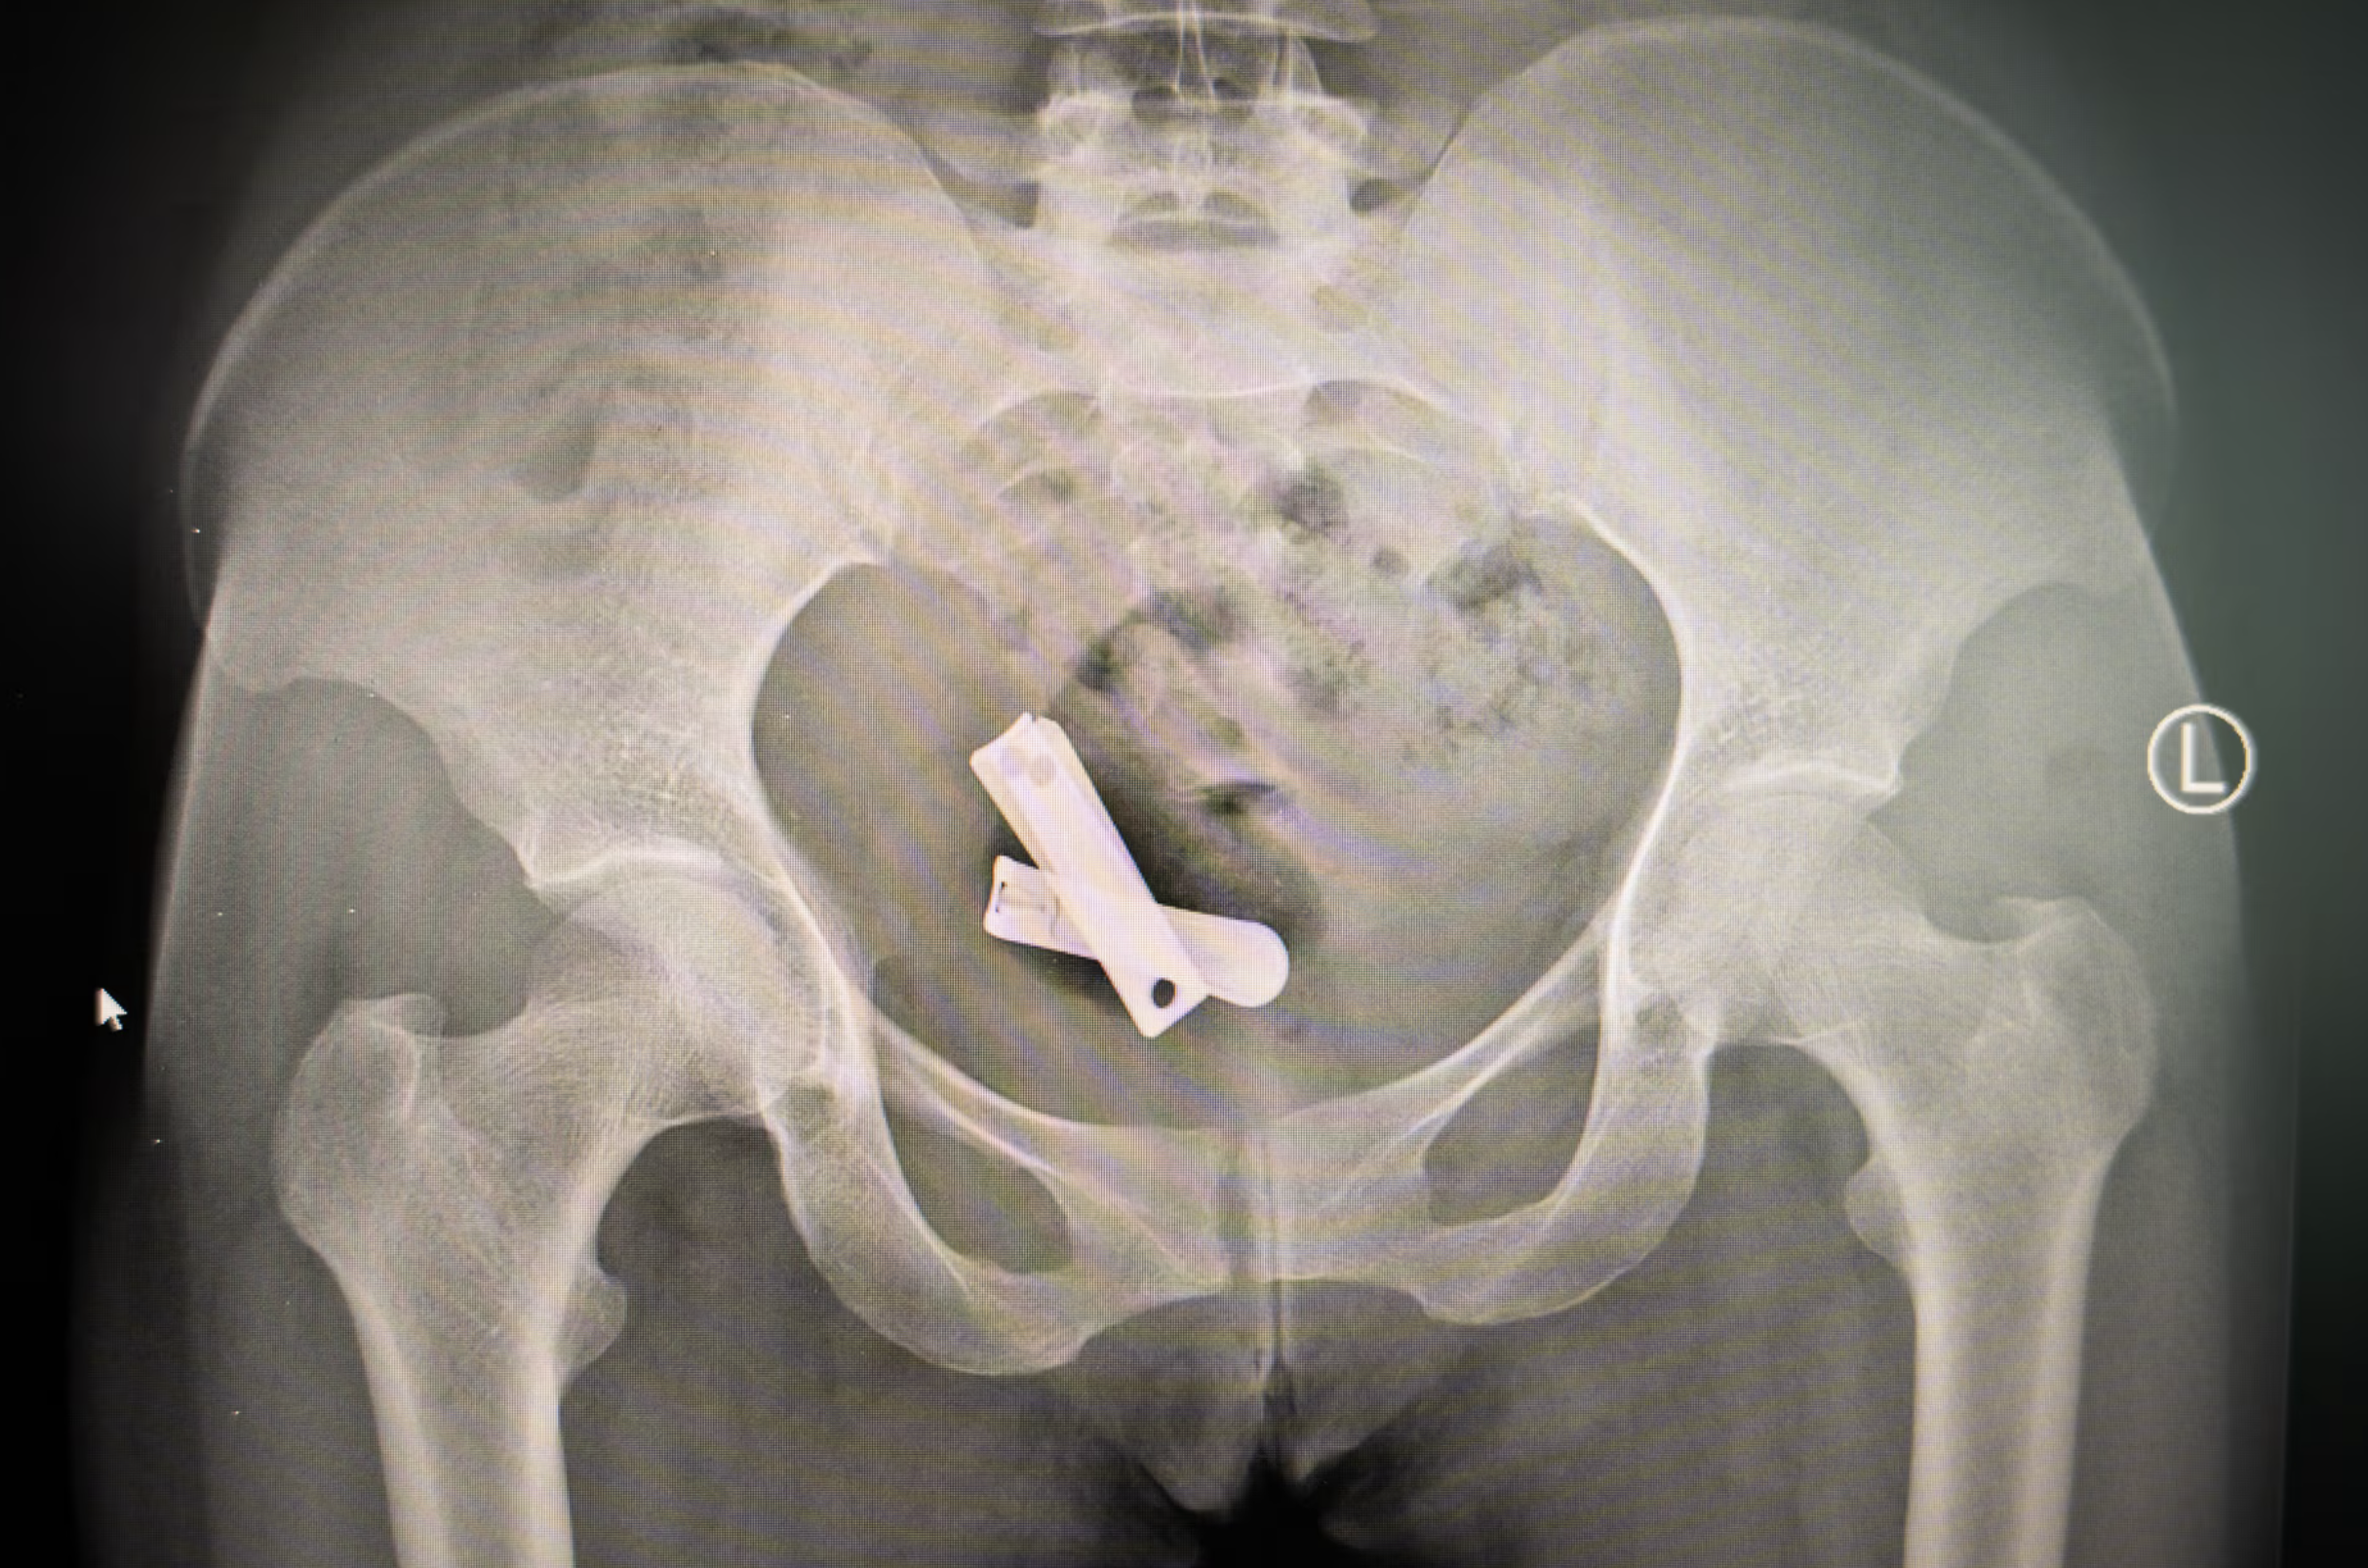

Deze röntgenfoto laat nagelknippers zien in de baarmoeder van een vrouw. Foto: Ximena Borrazás

Soms zijn de complicaties na een verkrachting zo ernstig, dat slachtoffers uiteindelijk toch naar een ziekenhuis gaan. Een speciale afdeling in het Ayder-ziekenhuis in Mekele, de hoofdstad van Tigray, behandelde de afgelopen jaren meer dan 7000 vrouwen en meisjes. Sommigen blijken objecten in hun baarmoeders te hebben, zo brengt de Britse krant The Guardian naar buiten.

In een kliniek in de Tigrese hoofdstad Mekele laat een verpleegster een röntgenfoto zien waarop te zien is dat er vreemde objecten in een baarmoeder zijn gevonden.